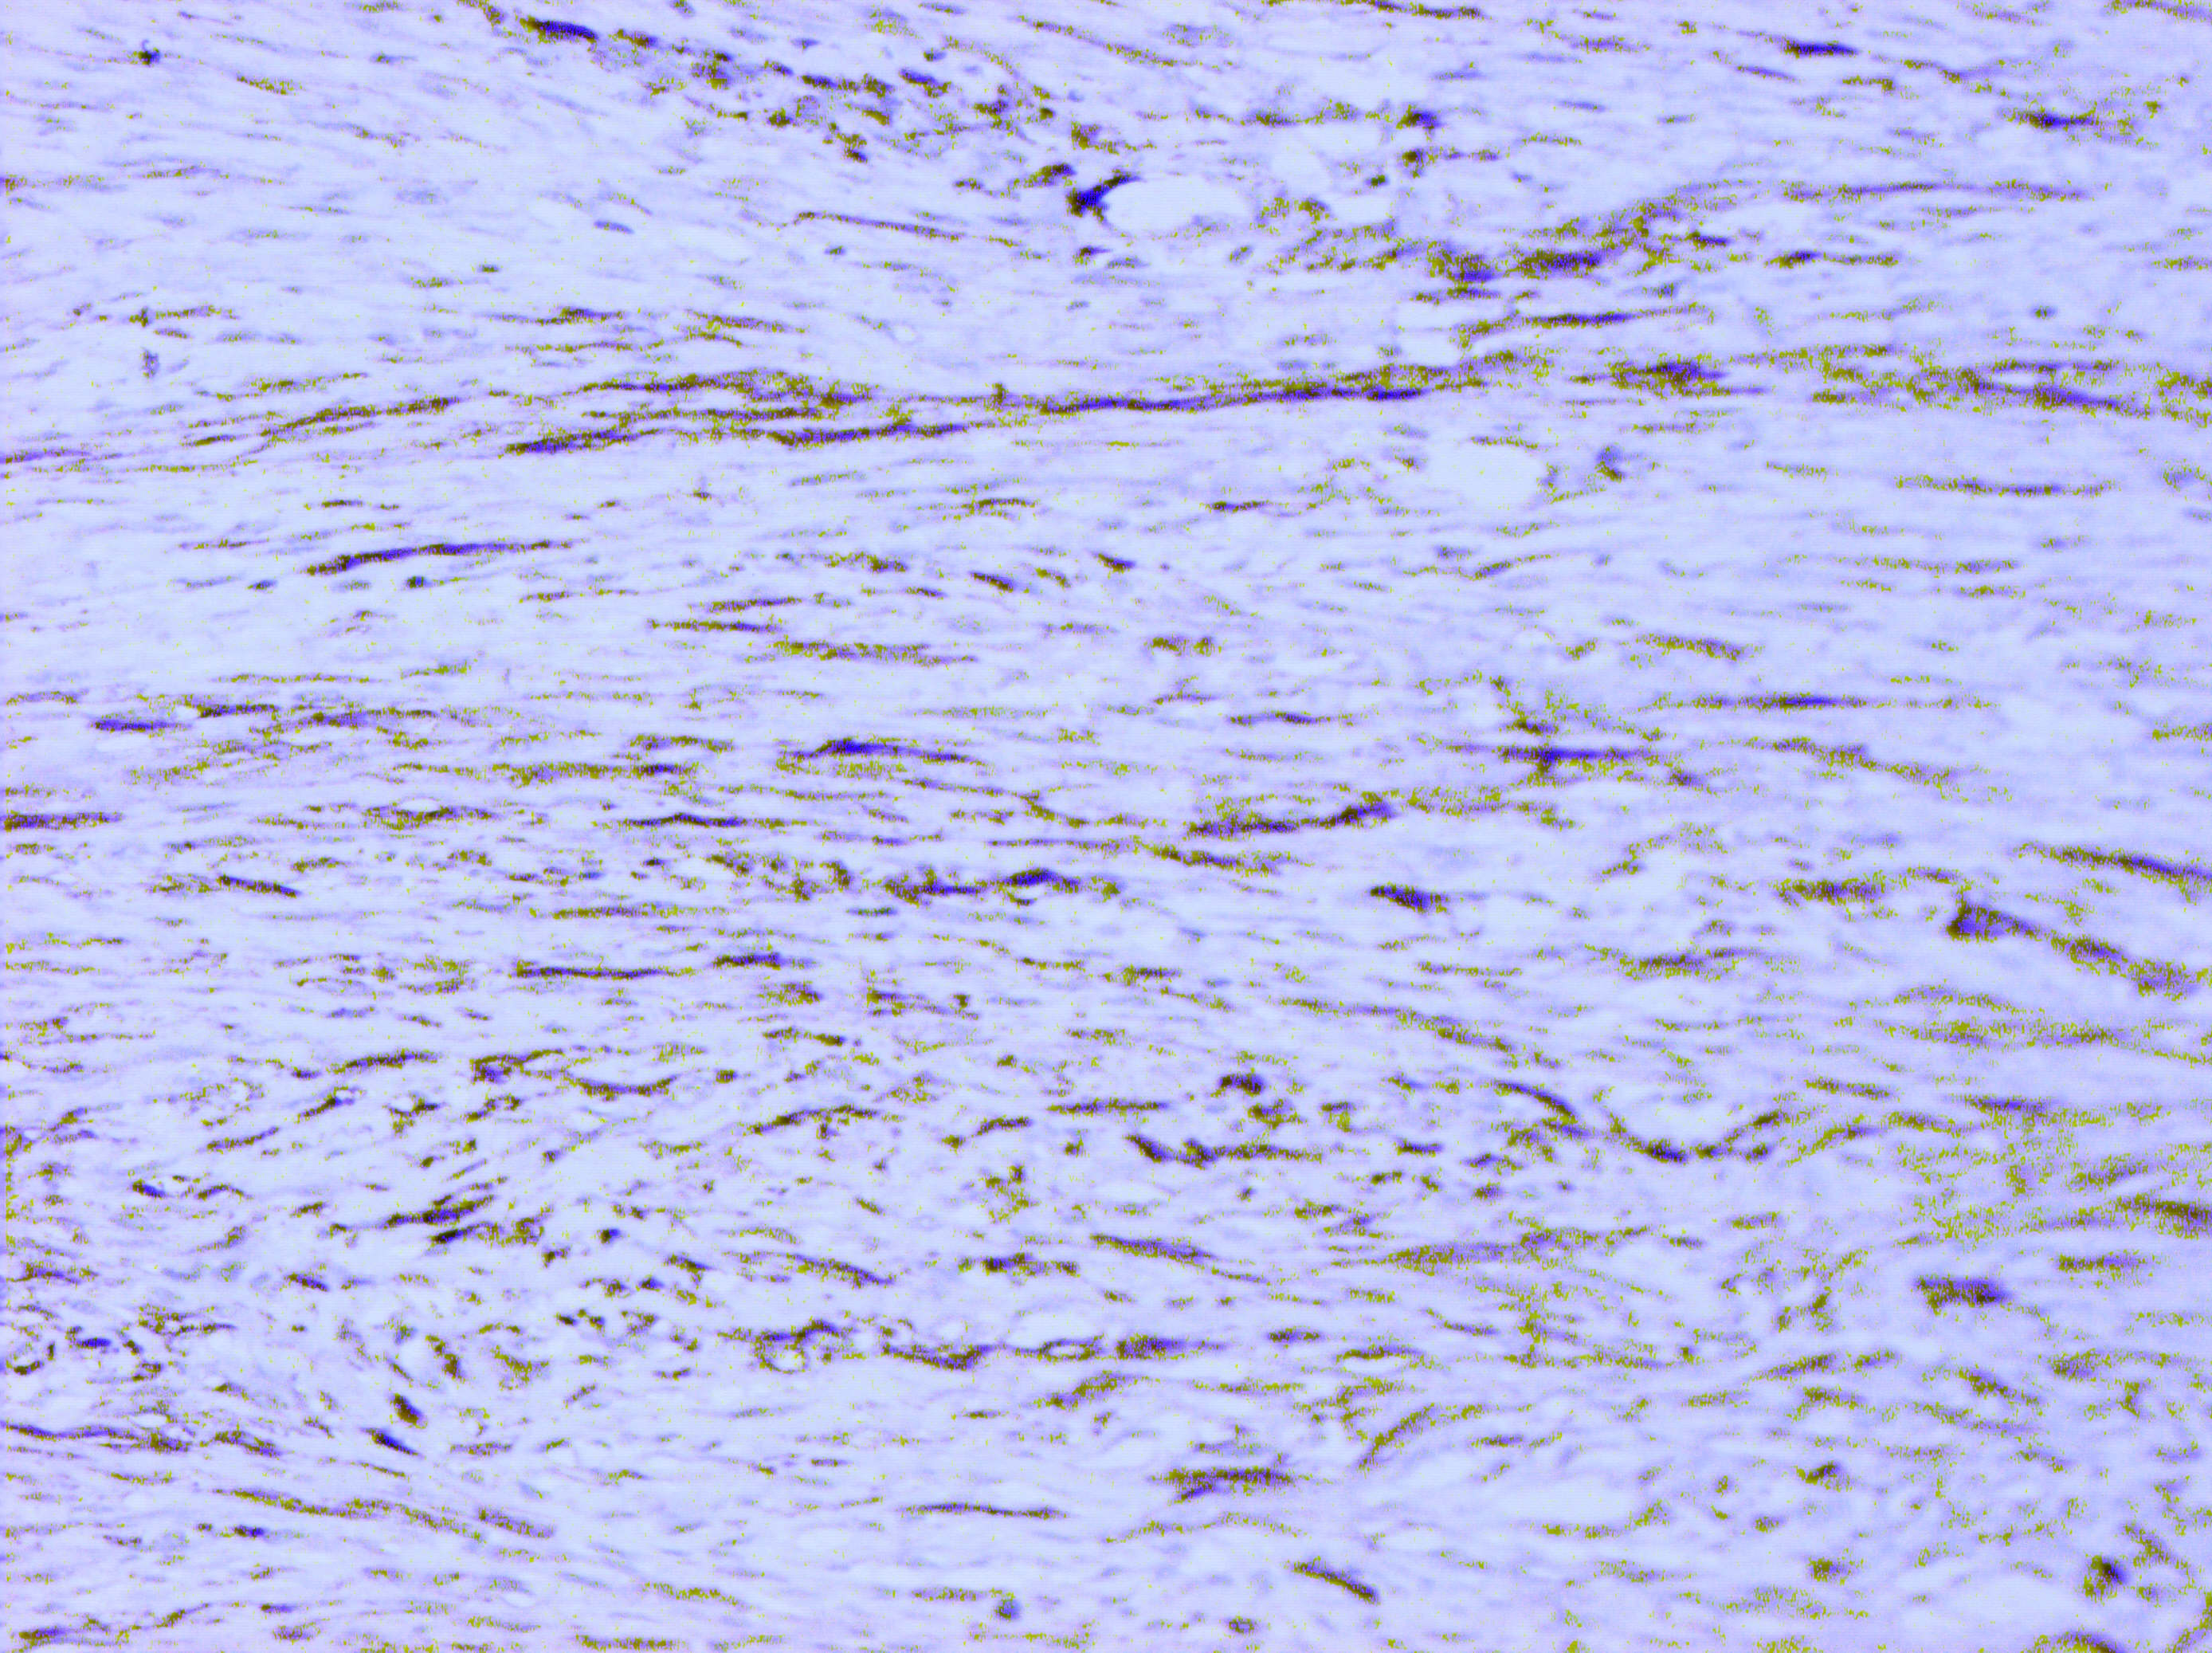

Матеріали та методи. Для ІГХ-дослідження було відібрано 60 парафінових блоків пухлин, у яких гістологічно було верифіковано діагноз саркоми (42) та філоїдної пухлини (18). ІГХ-дослідження проводили з використанням спектра відповідних антитіл, який включав маркери панцитокератинів (клон AE1/AE3); ERG (клон EP111); SOX-10 (клон EP268); TLE1 (клон 1F5); кальдесмону (клон h-CD); міогеніну (Myf-4) (клон F5D); MyoD1 (клон EP212); десміну (клон D33); MDM2 (клон 1B10); CDK4 (клон EP180); CD68 (клон PG-M1); CD34 (клон QBEnd 10); CD31 (клон JC70A); бета-катеніну (клон betaCatenin-1); гладеньком’язового актину альфа (клон 1A4); актину (клон HHF35); епітеліального мембранного антигену (EMA, MUC1) (клон E29). Також визначали рівень експресії маркера проліферації Ki-67 (клон MIB-1). Дослідження проводили в лабораторії CSD Health Care, м. Київ.

Результати дослідження та їх обговорення. Після проведених імуногістохімічних досліджень виявилось, що із 12 сарком без уточненого гістотипу в 9 випадках були плеоморфні саркоми, у 2-х – міофібробластні саркоми, та одна остеосаркома. Із 27 блоків ангіосарком імуногістохімічно було підтверджено 17 (63,0 %), інші 10 (37,0 %) виявились карциномами. Фібросаркоми (три гістологічні блоки) були повністю підтверджені імуногістохімічно. Серед 18 гістологічних блоків філоїдних пухлин проміжного типу у двох випадках (11,1 %) було встановлено злоякісний варіант ФП.